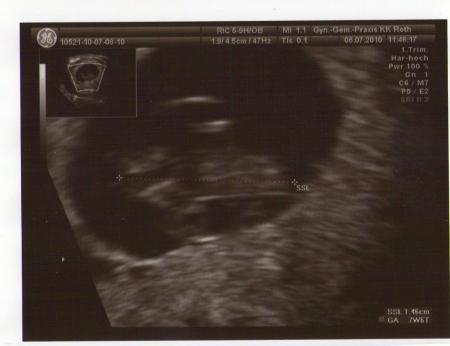

hey, versuch dir nicht so schlechte gedanken zu machen ich hatte am anfang meiner schwangerschaft über 1 woche blutungen, teilweise sogar periodenstark. dachte ich hab das kind verloren, aber im gegenteil gestern beim fa war alles in ordnung, herz schlägt und alles ist in ordung vielleicht bekommst du von deiner ärztin urogest tabletten, dadurch ist bei mir die blutung total verschwunden. ich wünsch dir aufjedenfall viel glück, im anhang noch ein US bild von gestern liebe grüße aus den februar 2011 bus nadine

Süßes bild! Habe nur seit heute morgen so zieheim im rücken-wie bei der Periode..Oh mann..Wenn nur schon Montag wäre.